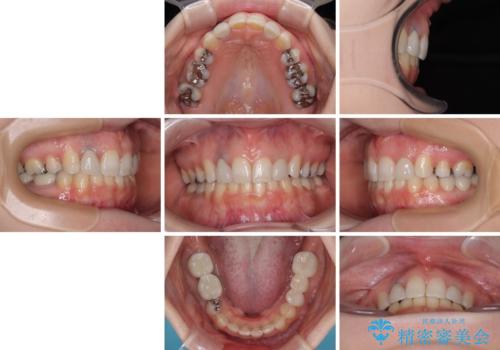

飛び出した上顎前歯とむし歯の多い歯列 目立たないハーフリンガル矯正とむし歯治療

抜歯したスペースがなかなか閉じず、治療に時間はかかりましたが、術前術後のむし歯治療と合わせて3年10ヶ月で治療を終えることができました。

途中結婚により遠方に引っ越しをされたため、むし歯治療は取り急ぎ目立つところをセラミッククラウンとしましたが、今後落ち着いてきたら他の部分も行っていく予定です。